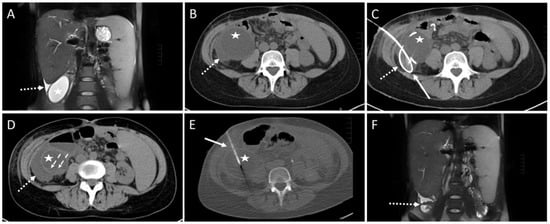

Figure 2. Example of a routine CT-guided drainage placement without complications. A 50-year-old man with history of liver transplantation due to alcohol-induced cirrhosis. Five weeks after surgery, an increase in transaminases and serum bilirubin was observed. Later, a palpable mass and upper abdominal pain developed. (A) CT planning scan 59 days after transplantation showed a large subcapsular fluid collection with mass effect encompassing the anterior liver margin (arrowheads). (B) CT fluoroscopy scan: An 8F drain (arrow) placement in the collection (arrowheads) via a left anterior transabdominal access using the Trocar technique was performed. (C) Maximum-intensity projection (25 mm slab thickness) of the CT control scan revealed a marked reduction in the mass effect. It was possible to aspirate 3000 mL of yellow-green fluid, resulting in almost complete drainage of the formation. Only a small residue (arrowheads) remained in the left recessus. Patient reported instant relief of symptoms (dotted arrows: collapsed abdominal wall, arrow: drain). No signs of complications such as organ penetration or bleeds are visible. Microbiological analysis revealed a sterile biloma. (D) Eight years later, the patient was readmitted due to cholangitis of the left liver lobe with several abscesses (arrowheads). (E) Again, CT-guided placement of two drains (arrows) could be successfully performed. The additional administration of pathogen specific antibiosis led to a decrease in inflammatory parameters. Arrowheads: Abscesses.